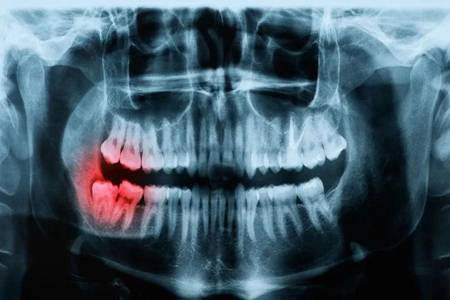

智齿一定要拔吗?智齿出现发炎肿痛时再不拔就晚了

智齿一定要拔吗?在说起这个问题的时候,许多小伙伴们最想看到什么样的回答呢?可能许多小伙伴们都会觉得拔牙特别的疼,于是抱有着侥幸心理想着要是看到不一定非拔不可的文章,那就蒙混过关吧。

如果你觉得智齿对于口腔问题没有影响,那么就可以不用去拔掉啊。但若是,智齿发炎肿痛的话,还不去拔?等着过年?

一时的疼痛要比一生时不时滋滋的疼好受吧?而且拔牙也没那么疼,第一步就给你上了麻醉,再加上现在的麻药工具也是在不断地更新,所以说只需要配合医生的操作,真的不是很疼。

看到这里,你可能要跃跃欲试的去拔牙了?别着急,虽然说牙齿能够顺利的拔除,但是之后也需要我们做好措施才行,不然的话很有可能出现“干槽症”哦!

这绝对不是吓唬你,因此,建议小伙伴们想要去拔掉智齿的话,在拔牙之前之后一定要选好医院以及专业的医生,之后配合医生,拔牙之后一定要谨遵医嘱,做好清洁工作,以免出现干槽症之后还要找医生进行二次清创。